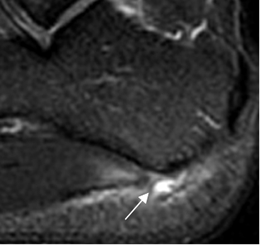

Su ruptura generalmente ocurre en una fascia inflamada y asociada a infiltración local de esteroides. Se observa como solución de continuidad con o sin retracción, edema y hemorragia. (6). (Fig 117).

Fig 117. Ruptura parcial.

RM sagital en STIR. Ruptura parcial de la fascia a nivel de su inserción (Flecha), con cambios inflamatorios periféricos.